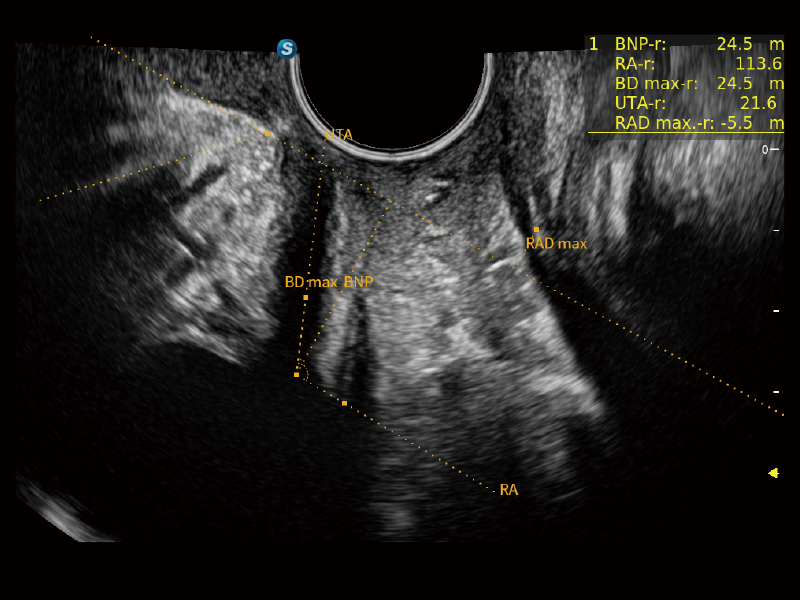

丰富的血流动力学检测技术,可在不同医疗场景中高效捕捉血流信号,助力临床诊疗。

在传统血流的基础上优化扫查和算法策略,能够更好的抑制组织信息,提炼红细胞运动信息,得到更高帧频,高灵敏度和分辨率的血流信号,还原更真实的血流动力学。

通过光照模型,使二维血流显示出立体的效果,增加血流的敏感性、成束性,减少外溢。可以和其他不同的血流技术联合使用,融合不同技术的优势。轻松应对微小血管,增强血流的立体效果,提升视觉敏感性。

通过创新的Matrix E自适应滤波算法,能有效滤除软组织和噪声信号,最大限度保留超低速微细血流的信号;结合超长时间域算法,极大提升细微血流的敏感性和空间分辨率,更真实的反应组织、包块的血流灌注情况。